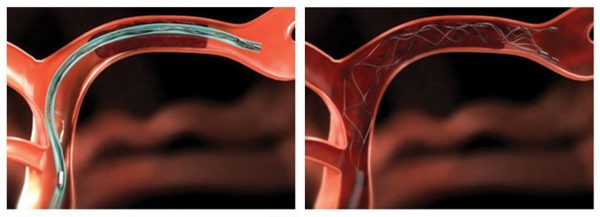

Η θρομβοεκτομή

Η θρομβεκτομή είναι μια σωτήρια επέμβαση για ασθενείς με οξύ εγκεφαλικό επεισόδιο, που πρέπει να πραγματοποιηθεί άμεσα, συνήθως εντός των πρώτων έξι ωρών από την έναρξη των συμπτωμάτων του επεισοδίου. Εφαρμόζεται για την απομάκρυνση του θρόμβου που έχει αποφράξει ένα αγγείο στον εγκέφαλο, και ο οποίος δεν έχει διαλυθεί, παρά τη χορήγηση θρομβολυτικών φαρμάκων.

Ο γιατρός τοποθετεί ένα λεπτό καθετήρα στην αρτηρία του ασθενούς, συνήθως μέσα από τη βουβωνική χώρα, και στη συνέχεια τον προωθεί μέχρι τα αγγεία του εγκεφάλου, όπου βρίσκεται ο θρόμβος. Στη συνέχεια, είτε με την τοποθέτηση ενός μεταλλικού πλέγματος, είτε μέσω αναρρόφησης ο θρόμβος απομακρύνεται μηχανικά από το αγγείο.

Αυτό αποκαθιστά τη φυσιολογική ροή του αίματος στον εγκέφαλο και μειώνει σημαντικά τη βλάβη που έχει προκληθεί, αποτρέποντας μακροχρόνιες, σοβαρές σωματικές και ψυχικές βλάβες στον ασθενή.